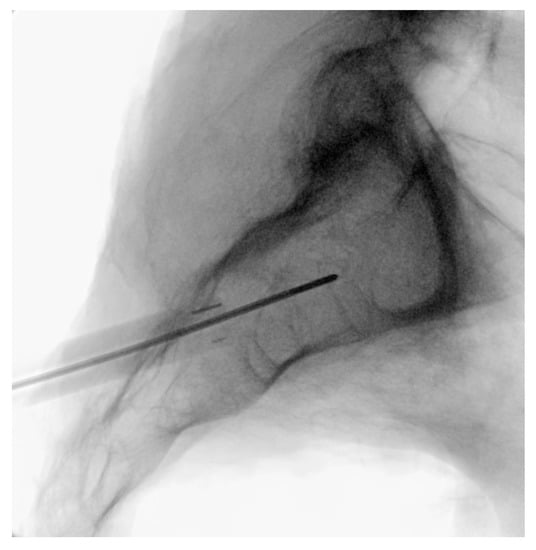

3.3.4. Steinman Pin Placement

3.3.5. Tissue Dilation